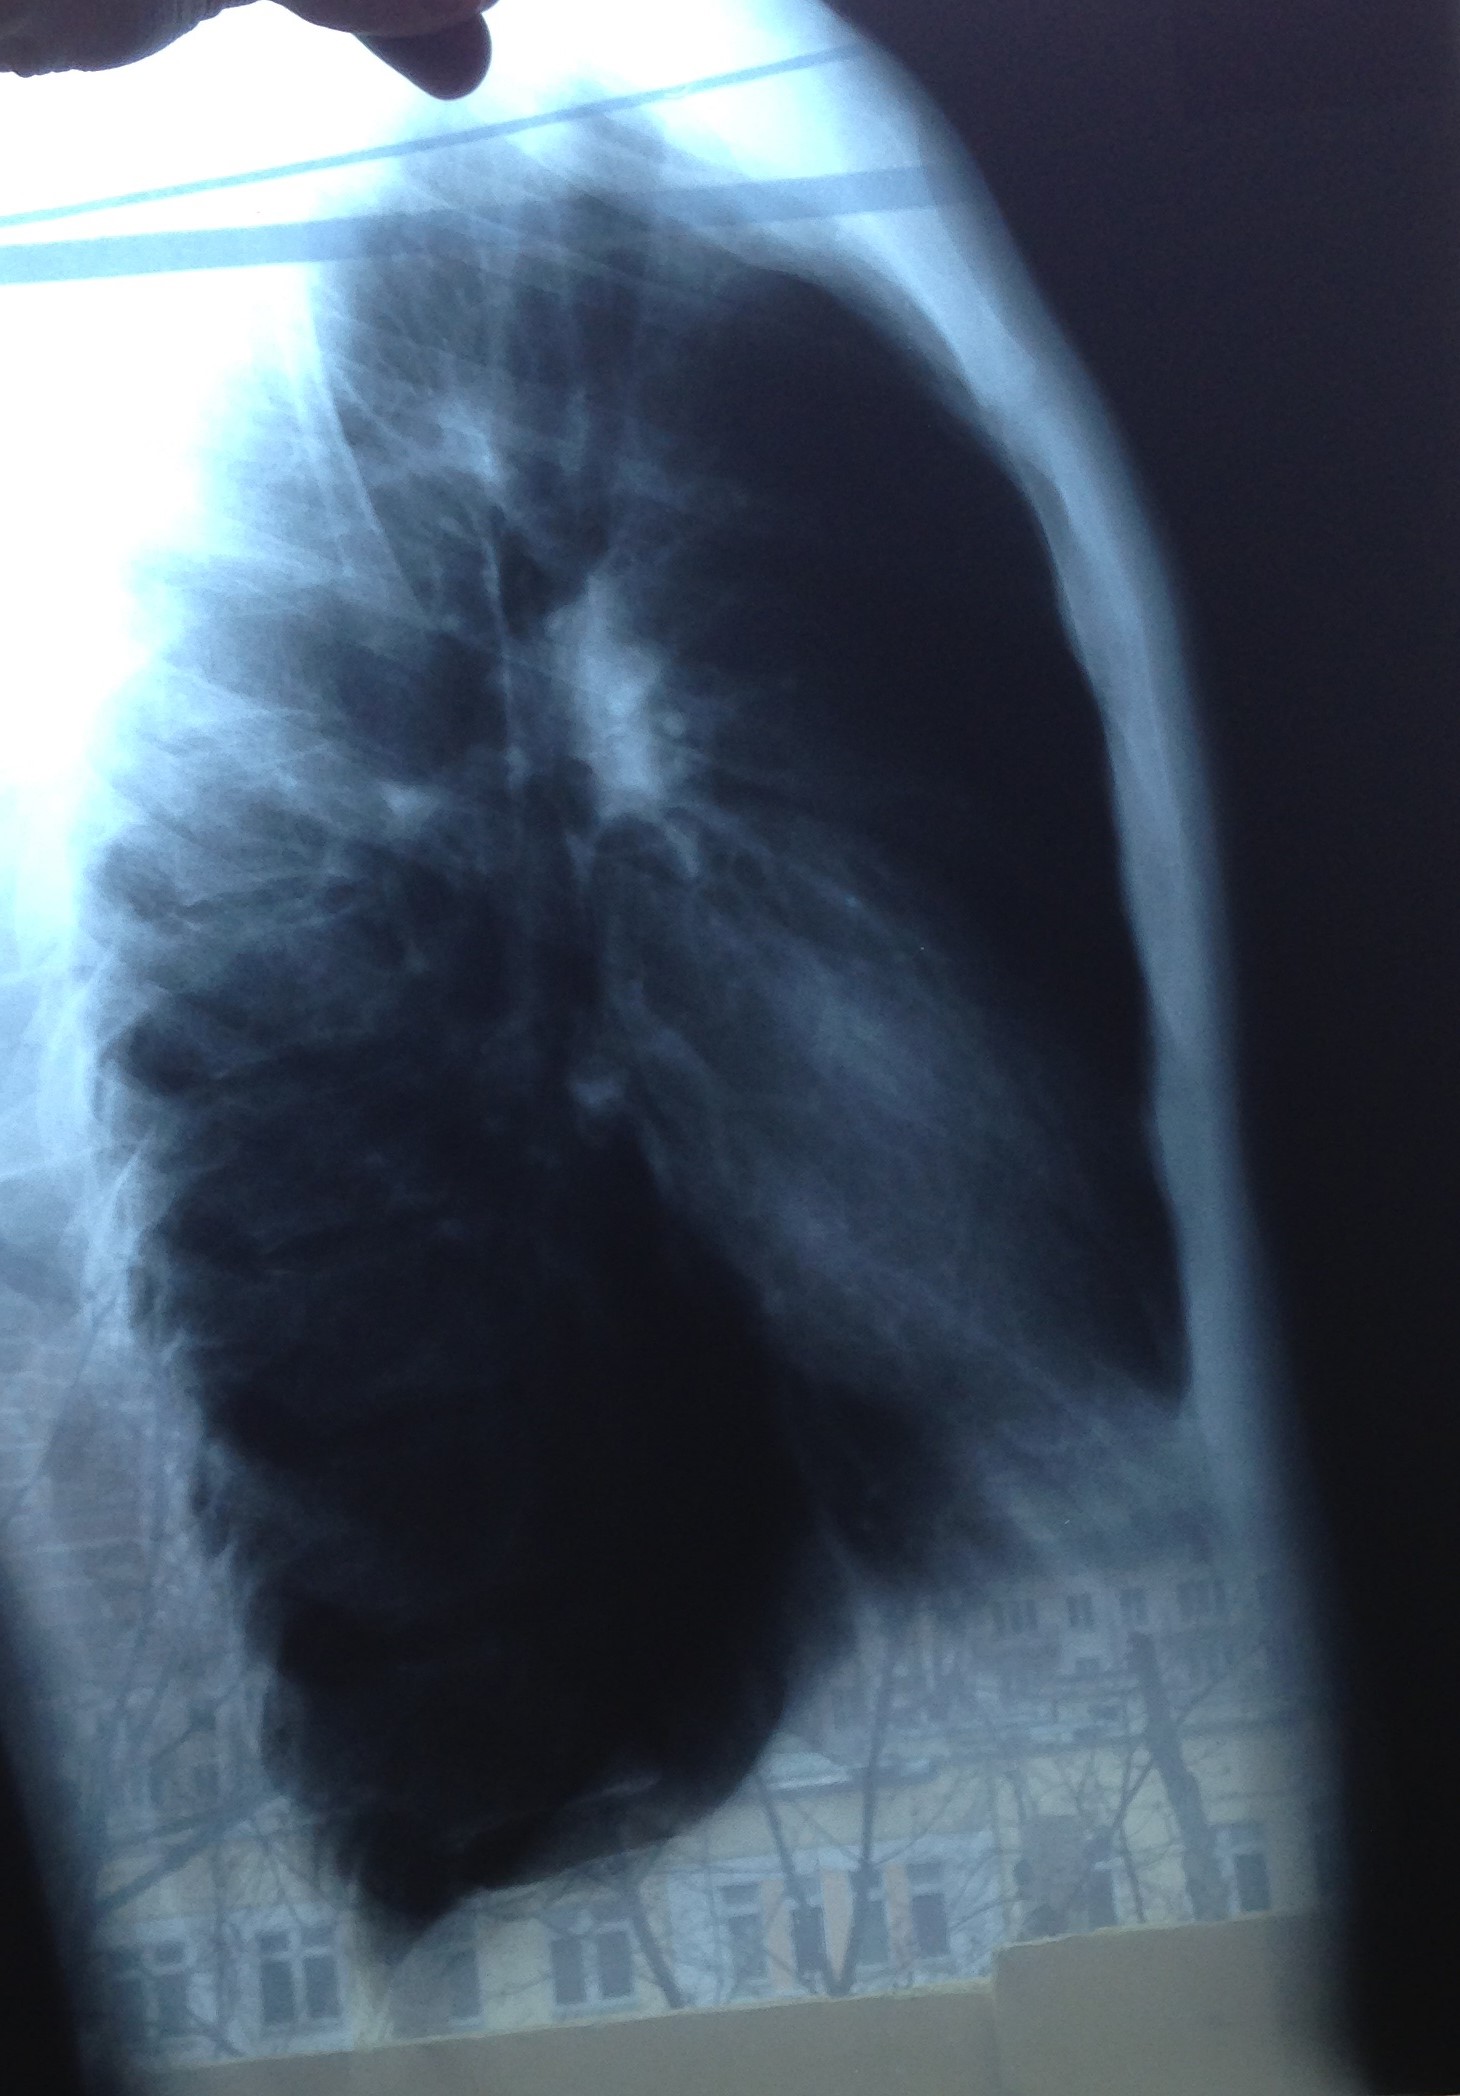

Сделал рентгенографию. Лечу бронхит муколитическим (ацц), пью много воды. Врач с которым консультировался сказал что противовирусные принимать поздно, а антибиотики пока не нужно, т.к. состояние более менее. Направил в диспансер проверить на туберкулез.

Можно ли что-то сказать по снимкам?

На фоне пейзажа на рентгенограмме трудно что-либо разглядеть, но на мой взгляд нормальные легкие. Рентгенолог много написала, видимо с фантазией все в порядке

Патологических изменений не определяю.

Извините за качество, лучше не удалось придумать источника света под нужным углом))